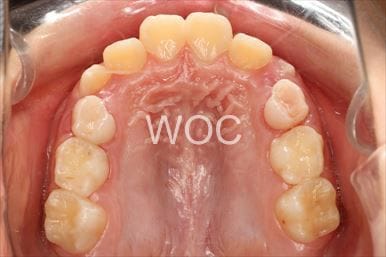

治療前1

治療前2

治療前3

治療前4

治療前5

- 年齢:23歳女性

- 主訴:出っ歯、口が閉じにくい

- 基本矯正料金:895,000円

- 治療期間:1年10ヶ月

- 非抜歯